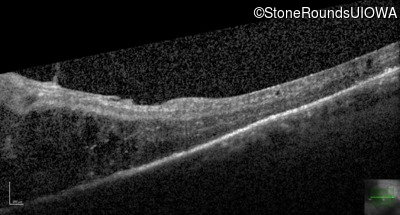

Optical Coherence Tomography - Left - 20/200 +2 sc

Exemplar / OCT Stack